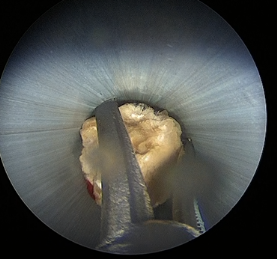

Ciltten böbrek içine bir yol oluşturulup konulan boru içinden endoskopik aletlerle taşın kırılması ve çıkarılması

Bükülebilir endoskopik aletin içinden geçirilen laserle taşın muhtelif büyüklükte küçük parçalara bölünmesi.